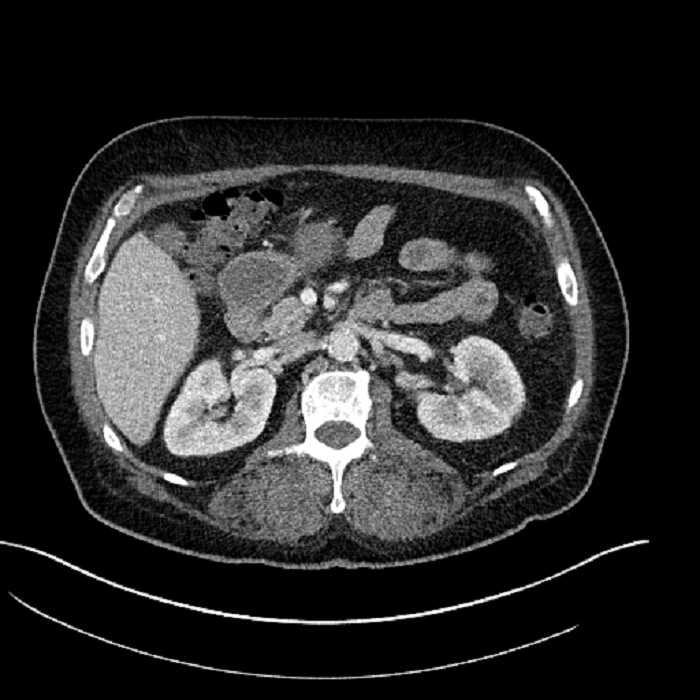

Age: 63

Sex: Male

Indication: Abdominal pain

• Large fluid density structure in hepatic segments 7 and 8 measuring 10 x 7 x 7 cm with internal septation and circumferential ill-defined low density compatible with edema

• Peripherally enhancing subcapsular collections along the anterior margin of the left hepatic lobe measuring 3 x 1 cm and 2 x 1 cm

• Clearly marginated fluid density structure in segment 7 and several other scattered tiny hypodensities, which likely represent cysts

• Hepatic abscess

Acute sigmoid diverticulitis complicated by a small contained perforation and a large abscess in the right hepatic lobe. Additional small subcapsular abscesses along the anterior margin of the left hepatic lobe.

• The classic CT imaging appearance is a double target sign with internal low density surrounded by an internal enhancing rim (capsule) and a low density external rim (edema)

Hepatic abscess showing the double target sign with low density internally surrounded by a thin inner enhancing rim (red arrow) and ill-defined outer low density rim (yellow arrow). Blue arrow indicates an internal septation. Red arrows: additional smaller subcapsular abscesses. Red arrow: focal contained perforation associated with diverticulitis.